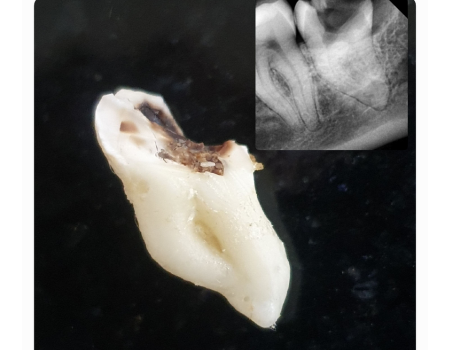

Wisdom Tooth Surgery

Safe, precise removal of impacted or problematic wisdom teeth to prevent pain, infection, and misalignment of surrounding teeth.